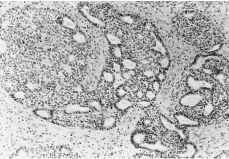

El estudio anatomopatológico definitivo informó de tumor de la granulosa quístico, variante adulta de 7 x 8 cm que no rompe la cápsula en ningún punto. (Figs. 1 y 2).

Figura 1.Tumor de células de la granulosa. En la porción superior se observan áreas microfoliculares típicas y en la parte inferior, zonas sólidas menos diferenciadas.

Figura 2.Se observan áreas microfoliculares y presencia de corpúsculos de Call-Exner.